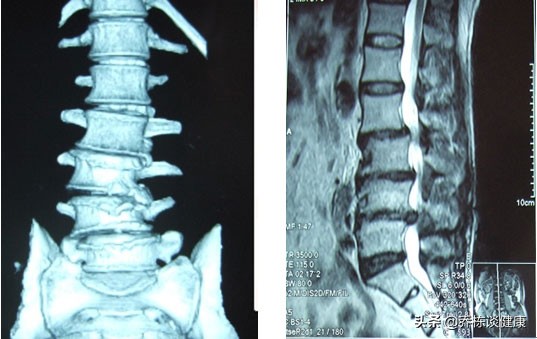

腰椎间盘突出,十几年前就开始出问题,然后每年都会因为腰部疼痛困扰,这是相当普遍的一种现象,是由于根本问题没解决好,或者说忽视腰椎间盘突出造成的并发问题,导致很容易受到刺激诱发症状。

- 谈到经常的出现腰腿痛,尤其是频发的腰痛,不应该只考虑腰椎间盘突出症,初期损伤的时候可能是这个原因,可是随着时间的增长,脊柱会逐渐稳定性变差,例如,出现腰椎小关节紊乱,腰肌劳损等。